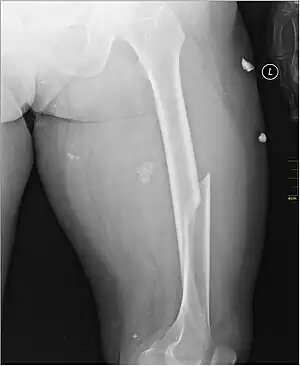

| X-ray image of a femoral shaft fracture | |

Radiography

Anterior-posterior (AP) and lateral radiographs are typically obtained.[4]

In order to rule out other injuries, hip, pelvis, and knee radiographs are also obtained.[5]

The hip radiograph is of particular importance, because femoral neck fractures can lead to osteonecrosis of the femoral head.[4]